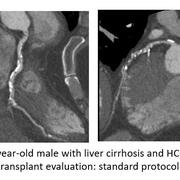

Pre-transplant liver and renal patients: The pre-transplant patients require coronary artery imaging to assess the risk of cardiac ischemia before major surgery such as the solid organ transplant. Unfortunately, standard coronary CTA imaging protocols yield suboptimal image quality in these patients due to their altered hemodynamic status. This results in either a suboptimal assessment of their pre-transplant risk or a need for invasive (and hence risky) imaging protocols such as coronary catheterization.

We developed two coronary CTA protocols tailored for those two distinct groups of patients:

2. Pre-renal transplant patients suffer from decreased injection fraction and severe coronary calcifications.  The major change that we implemented is the application of a bone algorithm to minimize the impact of artifacts caused by coronary calcifications.

Those protocols have shown that diagnostic CCTAs can be obtained in 90% of high-risk pre-liver and kidney transplant patients and have been incorporated into standard clinical care for pre-solid organ transplant patients.